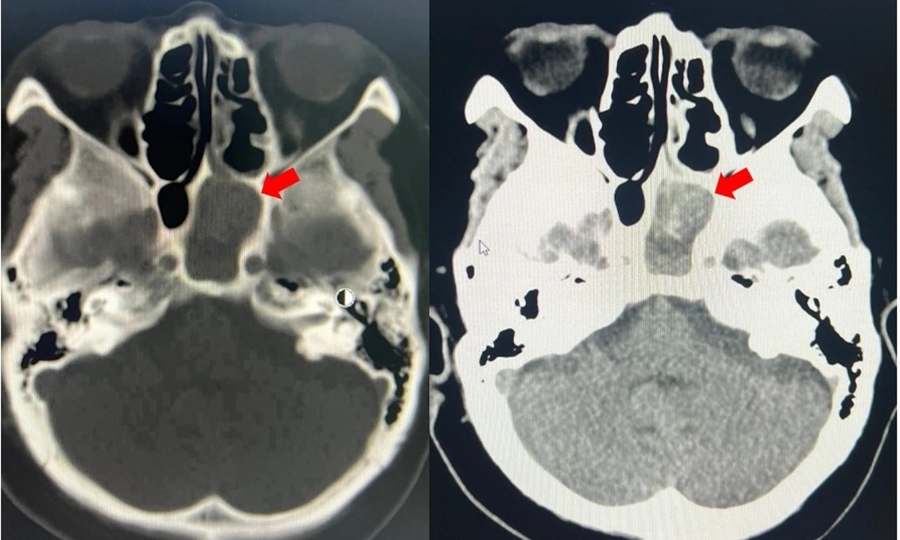

BSCKI. Nhâm Tấn Đạt cho biết, kết quả chụp CT scan và các xét nghiệm cho thấy người bệnh có khối nấm trong xoang bướm trái kèm nhiễm trùng xoang. Bệnh nhân đồng thời mắc tăng huyết áp, bệnh thận mạn giai đoạn III và đái tháo đường type 2 - những yếu tố làm bệnh dễ tiến triển nặng hơn.

Cũng vậy, sau hơn 1 tháng điều trị viêm xoang bằng thuốc nhưng cơn đau đầu không thuyên giảm, một người bệnh trẻ tuổi đã tìm đến Bệnh viện ĐKQT Nam Sài Gòn để điều trị. Trên film chụp CT, các bác sĩ phát hiện ổ nấm “ẩn mình” trong xoang bướm.

Ths.BSCKII. Nguyễn Trương Khương, Trưởng khoa Tai Mũi Họng bệnh viện, các dấu hiệu trên film CT để chẩn đoán nấm ở vùng xoang khá khó nhận biết. Các bác sĩ Tai Mũi Họng cần phải có chuyên môn và kinh nghiệm dày dặn để chẩn đoán, đó là lý do vì sao ở bệnh viện trước đây người bệnh thăm khám không tìm ra đúng nguyên nhân.